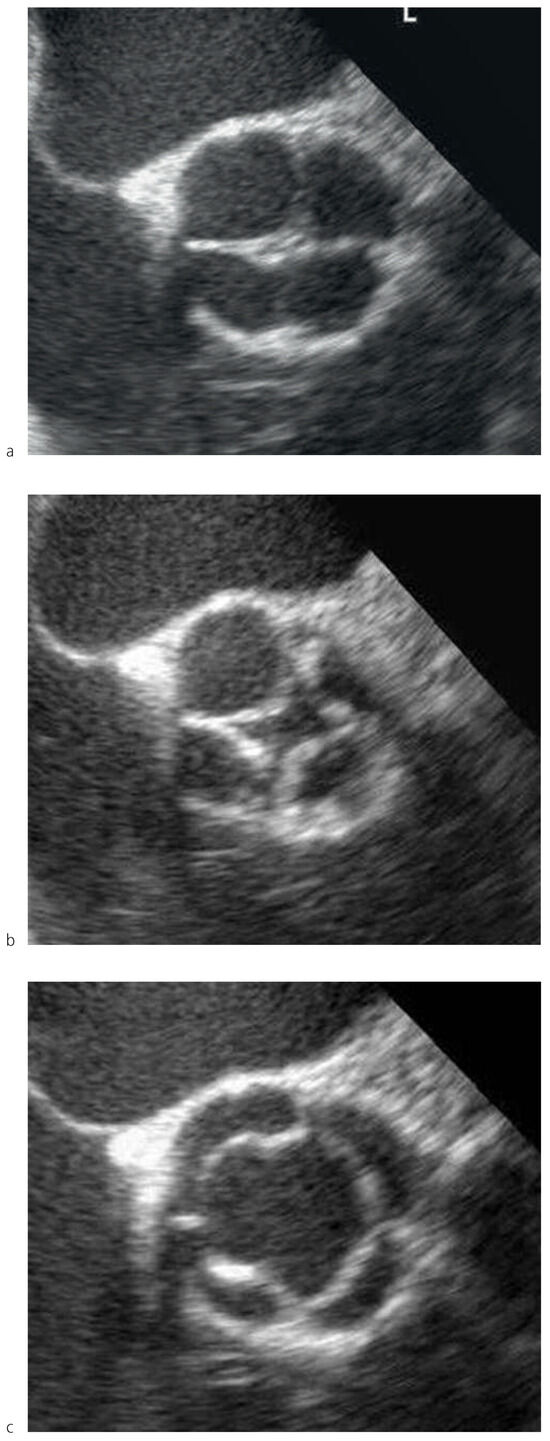

Dieser Befund bestätigte sich in der transösophagealen Echokardiographie (Figure 2a–c and Figure 3). Es fanden sich vier Kommissuren, welche periphere Fusionen der Taschen mit kurzen Raphen aufwiesen.

Figure 2. Transösophageale Echokardiographie: QAK in verschiedenen Phasen des Herzzyklus. Die geschlossene Klappe erinnert an ein Kreuz.

Die vier Taschen der QAK unserer Patientin waren symmetrisch konfiguriert, wenig verdickt und gut beweglich. Im Farbdoppler zeigte sich eine leichte zentrale Aorteninsuffizienz am Koaptationspunkt der vier Taschen. Der Hauptstamm der linken Koronararterie zeigte einen orthotopen Abgang. Nebenbefundlich fand sich ein PFO.